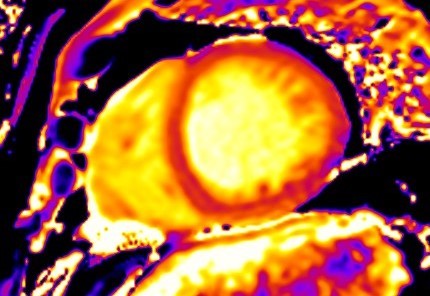

To overcome these limitations, T2 mapping, a parametric image of each voxel, was developed. T2 mapping values are independent of body size and/or heart rate and have good reproducibility [11]; however, they may vary between different scanner types or field strengths and for this reason the definition of individualized normal values for each center is strongly recommended [19, 20]. Increased signal on T2 mapping is an index of myocardial oedema, due to any kind of recent myocardial injury [11] (Fig. 4).

Fig. 4.CMR oedema evaluation using parametric imaging. T2

mapping in patient with polymyositis and ventricular arrhythmias (T2 mapping = 62

msec, normal values